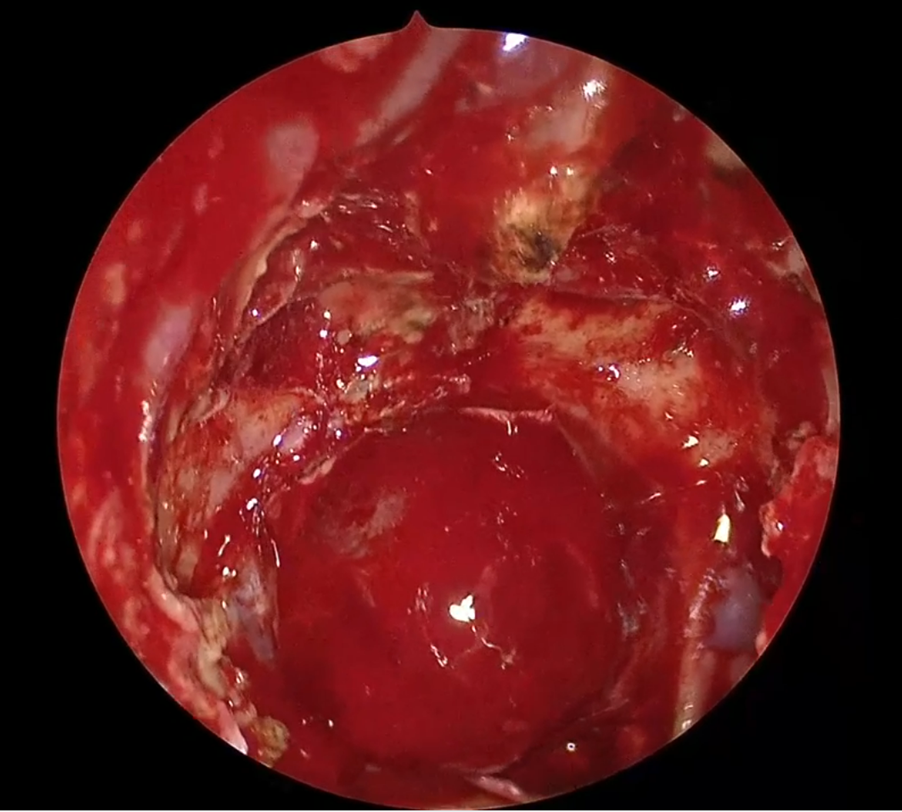

На заключительном этапе мы применили флуоресцентную ангиографию, когда выполнили пластику дефекта основания черепа. На начальном этапе операции мы забрали васкуляризированный назосептальный лоскут, а на завершающем этапе уложили его на область дефекта костей основания, выполнив тем самым реконструкцию, после чего ввели финальную порцию индоцианина зелёного. Мы убедились в том, что слизистая оболочка в области ножки лоскута контрастирует, что свидетельствует о сохранном кровотоке в этой области. Увидеть большего контрастирования по площади всего лоскута, нам не удалось. Не исключено, что эта погрешность связана с техникой забора лоскута, и возможно, что лоскут оказался либо частично, либо полностью деваскуляризированным в дистальной части, при сохранности кровоснабжения в области ножки.

👇 Листайте галерею влево.

Это еще одна из сторон применения технологии флуоресцентной ангиографии с индоцианином зелёным, которая позволяет оценить ткань, использующуюся для реконструкции. Васкуляризация назосептального лоскута — важный момент, который влияет на быстроту и эффективность заживления раны и приживления лоскутов в области дефекта основания черепа.